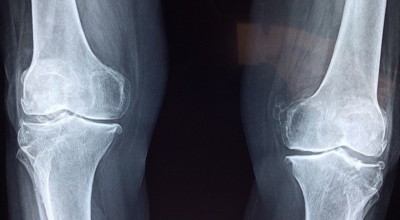

풍부한 보스웰릭산 성분은 염증을 억제하고 체내 연골 세포의 강화를 통해 초기 관절염, 퇴행성 관절염에 좋습니다. 또한 허리디스크 통증, 무릎 연골의 통증을 줄여주고 예방하는 데에도 효과가 있습니다. 시중에 판매되는 보스웰리아 제품들은 모두 이런 관절 및 연골 건강에 집중되어 있는데요 그만큼 보스웰리아 효능은 관절에 좋은 성분이 뛰어난 건강식품이라고 볼 수 있다고 합니다. 실제 한 연구결과에 따르면 관절염 환자 대상 보스웰리아를 8주간 섭취시 통증이 감소하고 무릎 붓기도 줄어들었다고 합니다.